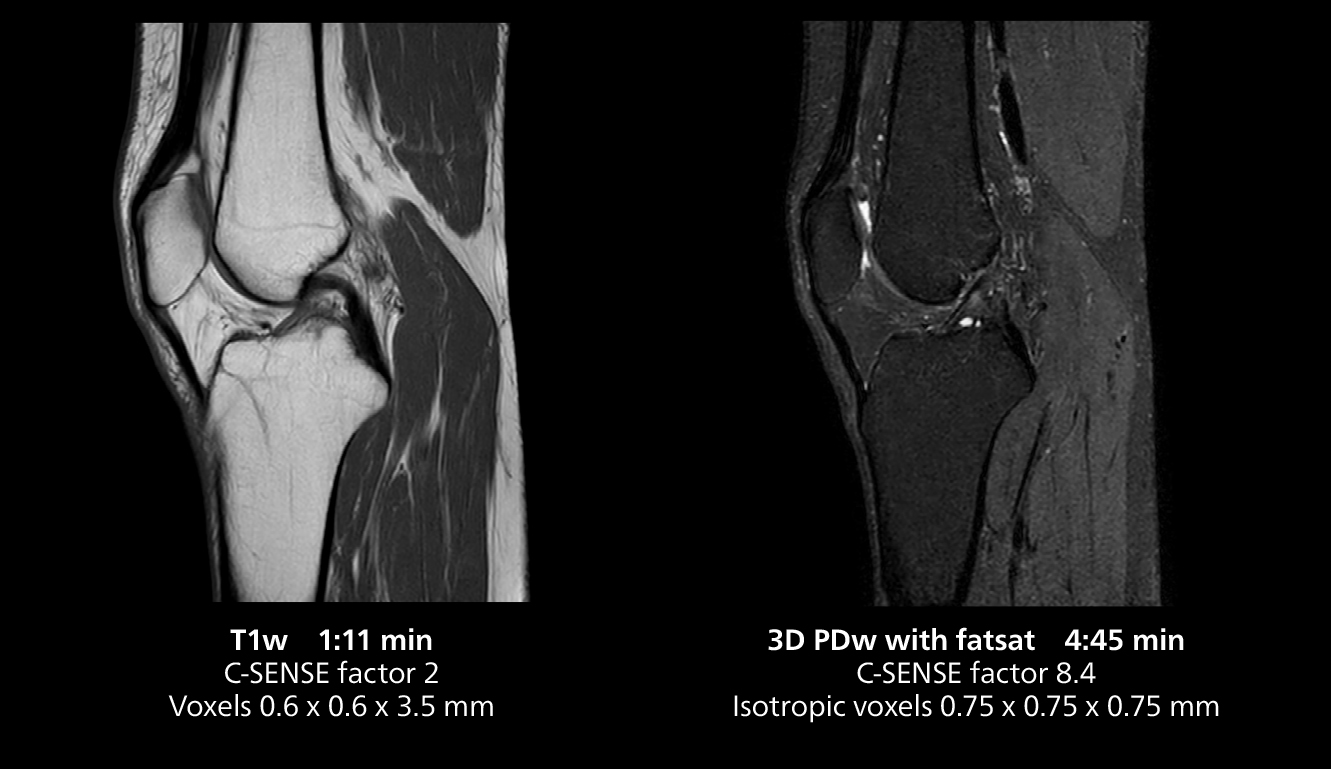

3D knee imaging

The isotropic high resolution 3D sequence in this MRI case allows for reformatting to obtain other orientations with high quality. Acquired on the MR 5300 system.